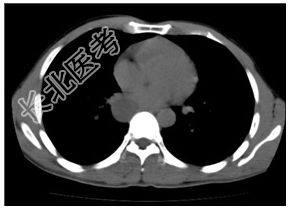

- [材料题] 患者,男性,31岁。阵发性胸痛多年,近来明显。查体:双肺呼吸音清,未闻及干湿性啰音。腹平软,肝脾未扪及。行胸部CT平扫及增强检查。

- 简答题1、患者的诊断及依据是什么?

- 简答题2、鉴别诊断有哪些?